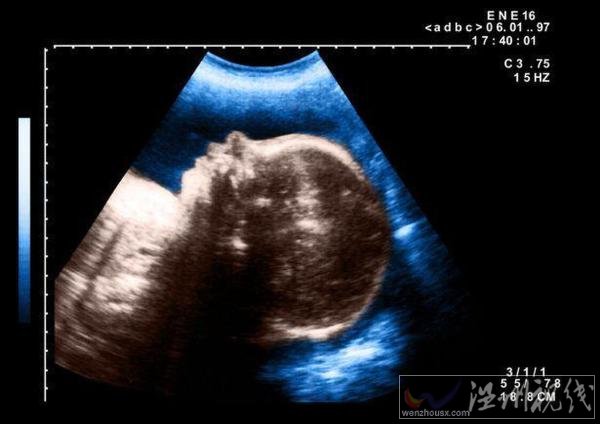

10月7日,埃及一名孕婦產(chǎn)下一個獨眼嬰兒,這個孩子在出生幾天后死亡。埃及嬰兒一只眼睛一時引起不少人關(guān)注,這名醫(yī)生猜測,可能是嬰兒在子宮內(nèi)受到放射物影響導(dǎo)致的畸形。

據(jù)悉,當(dāng)時這名醫(yī)生在被這個孕婦做檢查時,就發(fā)現(xiàn)她懷的這個孩子是一個嚴(yán)重畸形兒,但是沒想到會是這樣的。這個嬰兒出生時,只有一只長在中間的眼睛,在眼睛下面就是一張嘴巴。

醫(yī)生在對其做完接生后預(yù)計這個孩子活不過幾天,對于孩子畸形的原因,他認為應(yīng)該是受到放射物質(zhì)影響。